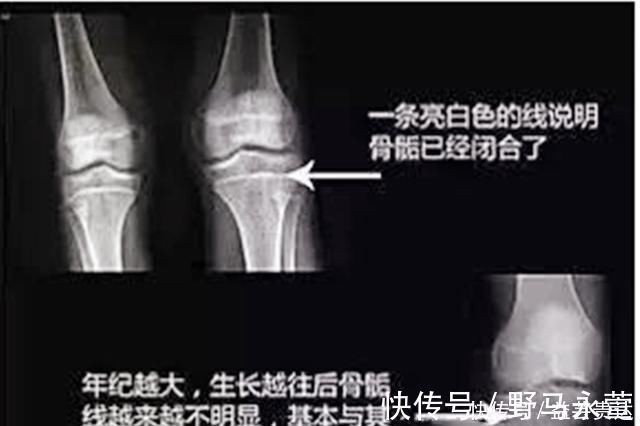

其实骨骼线就是骨骺和干骺端之间的软骨,在X光片中看起来就是一条透明带。人的年龄越大,骨骼线就会变得越短。等到软骨都骨化后就会变成一条缝。骨骼线闭合之后,骨骼就不会再生长了。